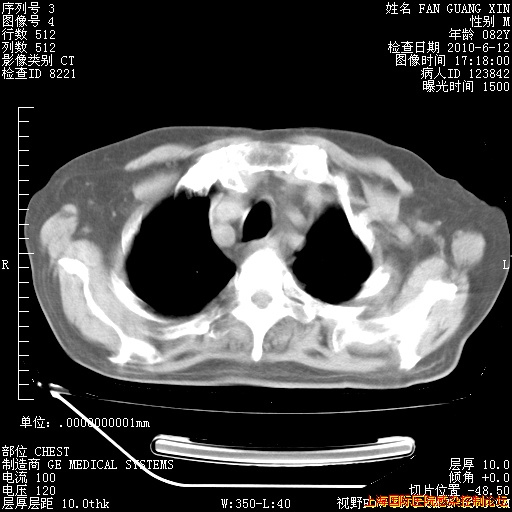

补发6月12日肺部CT肺窗

6月12日肺窗